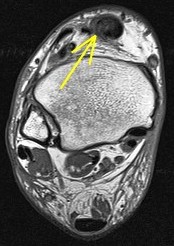

Figure 1 for case Gout arthritis ( RID3567 )

Figure 1